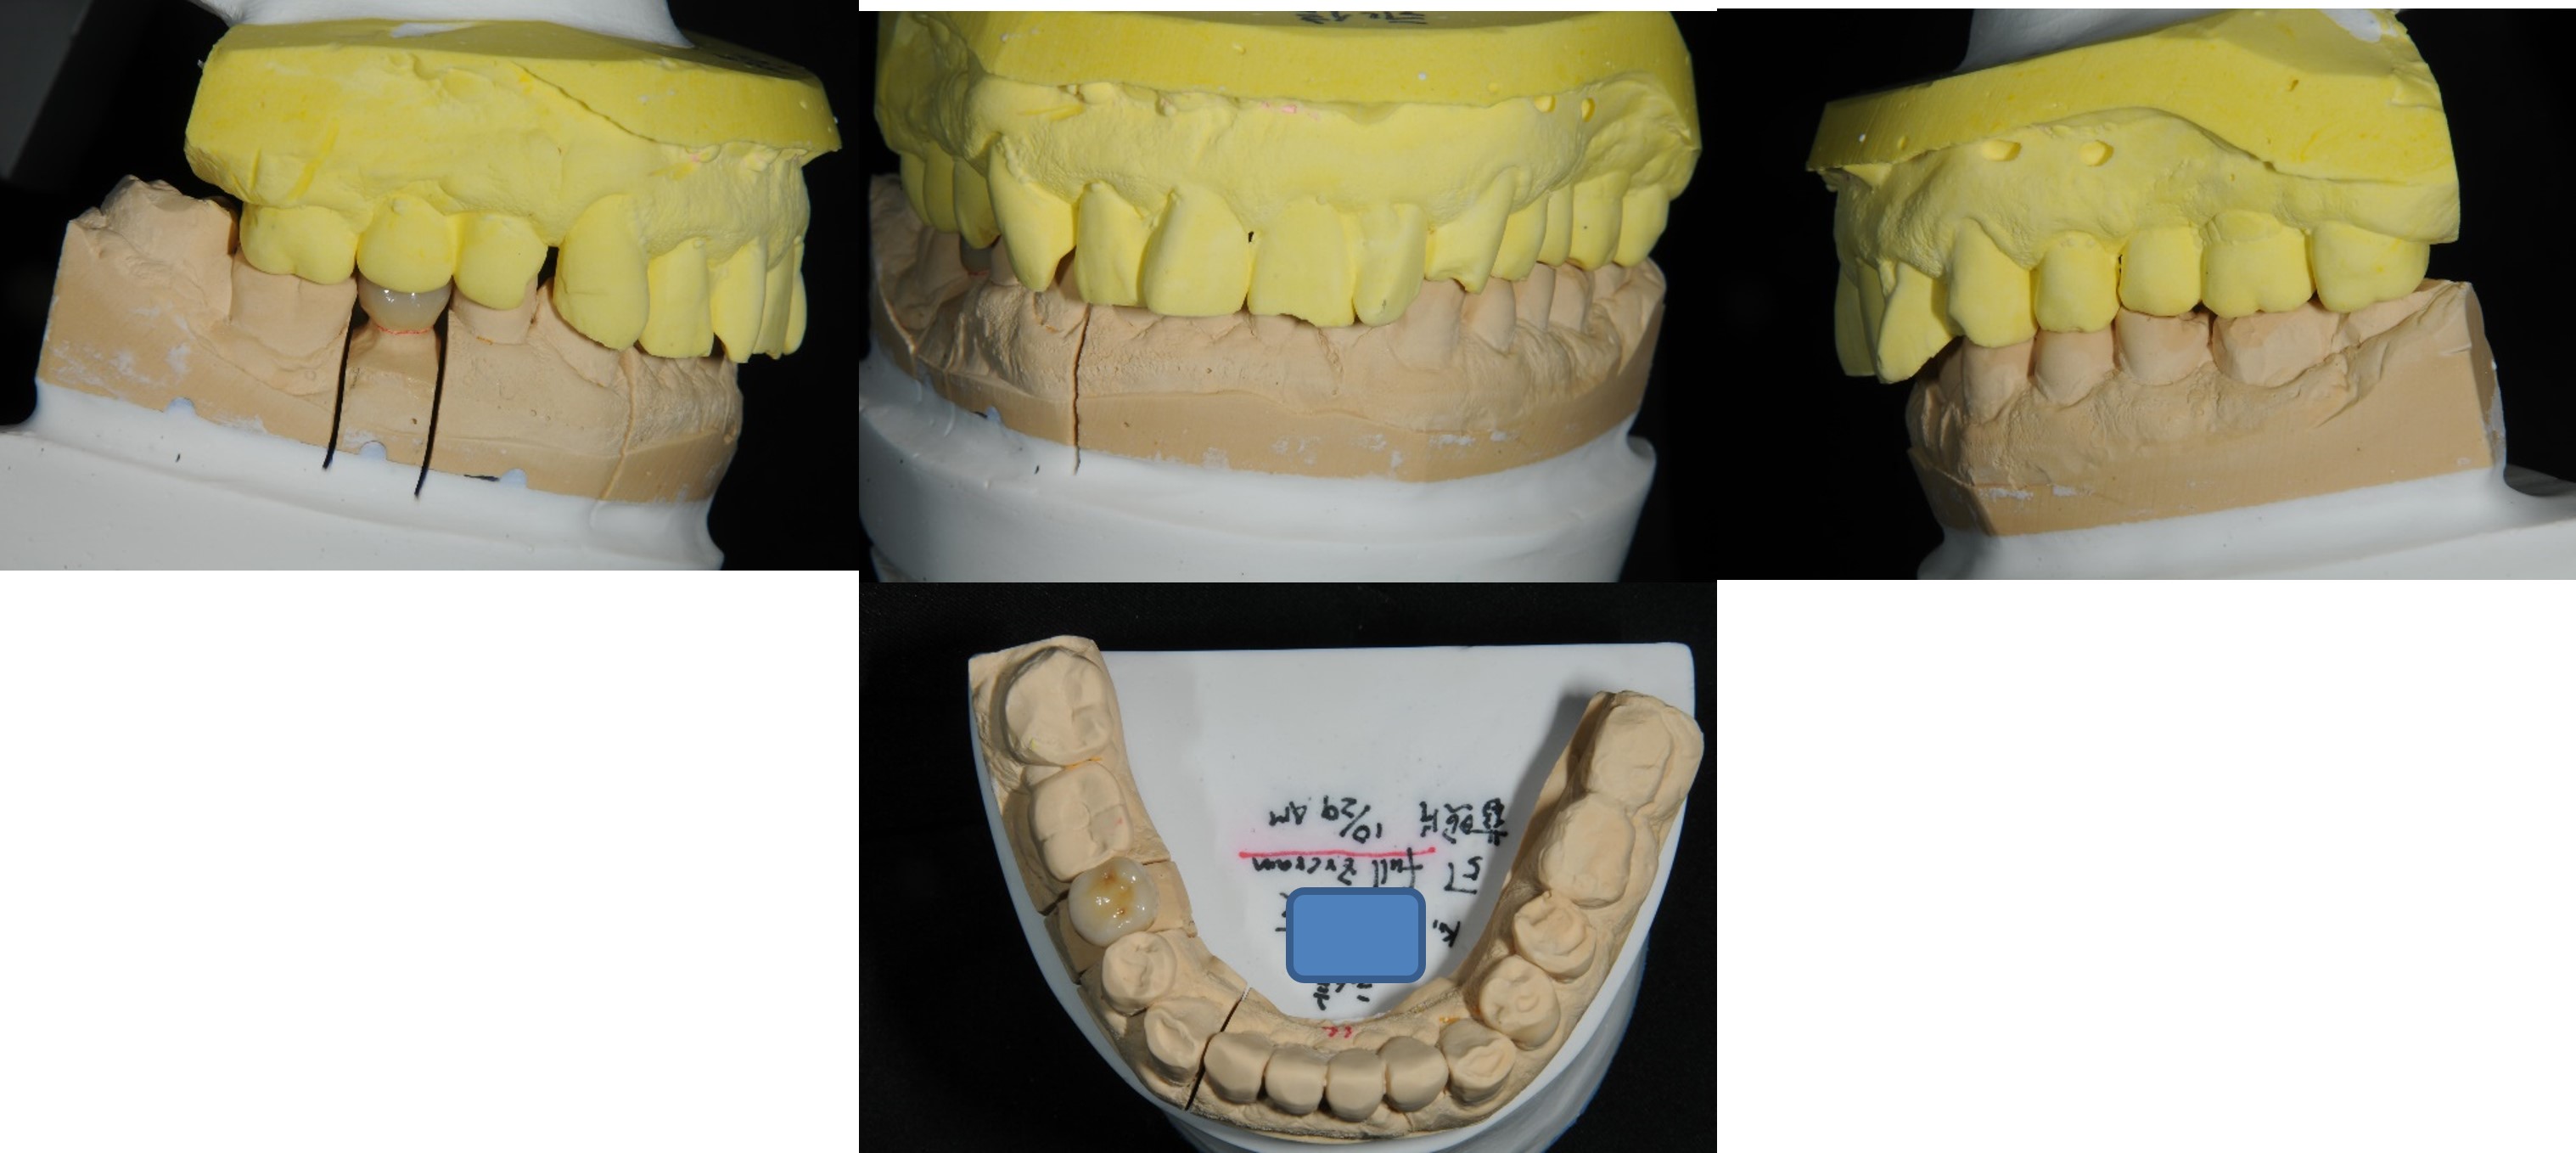

一體成型二氧化鋯全瓷冠

治療後口內照

患者的咀嚼機能逐漸恢復正常

治療後根尖照

透過牙冠修復受損結構,患者逐漸適應

術前、術後比較

幾年下來,這一類連續的治療,長期的癒後相當穩定,因此對於有心保留牙齒的患者,提供了另一個方法,是植牙之外的另一個重要的治療方式。